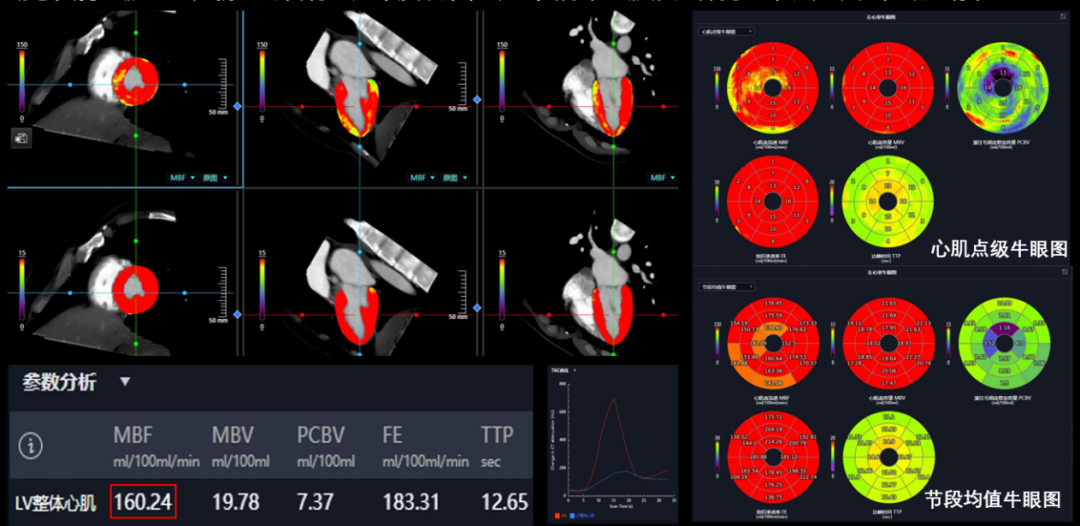

创新的全维心脏诊疗解决方案:

(1)16cm全心覆盖:实现无需动床的心脏冠脉检查;(2)一站式CTA+CTP多模态成像,提供心脏形态与功能的全维诊断信息,将供冠脉CTA、冠脉血流CT-FFR评估、以及心肌微循环功能学评估融为一体;(3)全栈AI:业内领先的智能化分析评估系统,将后处理时间缩短80-90%,且提高评估结果的精准性与可重复性。